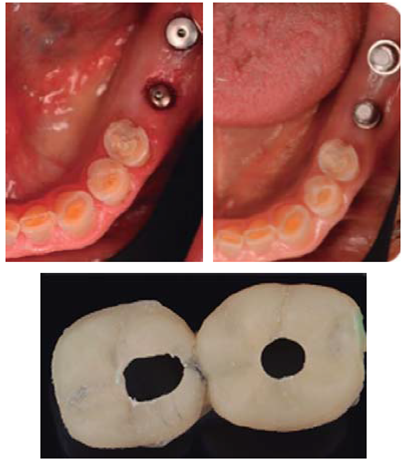

Este reporte documenta el tratamiento de un paciente masculino de 68 años de edad. Comenta tener dificultades masticatorias y digestivas debido a importante desgaste dental, se dice incómodo al sonreír; no refirió padecimientos sistémicos, fumó durante ocho años, diagnosticado con hipertensión arterial controlada. Se observa atrición generalizada, ausencia de dientes 14, 15, 16, 46 y periodonto sano (Figuras 1a4). Los dientes 13 y 37 presentaban tratamiento de conductos y periápice sano, sin restauración (Figura 5).

Se colocaron tornillos tapa y consiguiendo cierre sin tensión del colgajo, se suturó con seda 4Ø. Se prosigue a la provisionalización de los implantes previo descubrimiento (Figura 15).

Alcanzada esta etapa del tratamiento, se prosiguió con la planeación y colocación de implantes en zona de 14 y 16 de la marca Hiossen™ de 4 x 10 mm. La guía utilizada fue permisiva, los implantes consiguieron una estabilidad primaria de 30 N y ambos lechos fueron regenerados con 1 cm3 de aloinjerto óseo Biograft® y membrana de colágena RCM6® (Figuras 29a31).